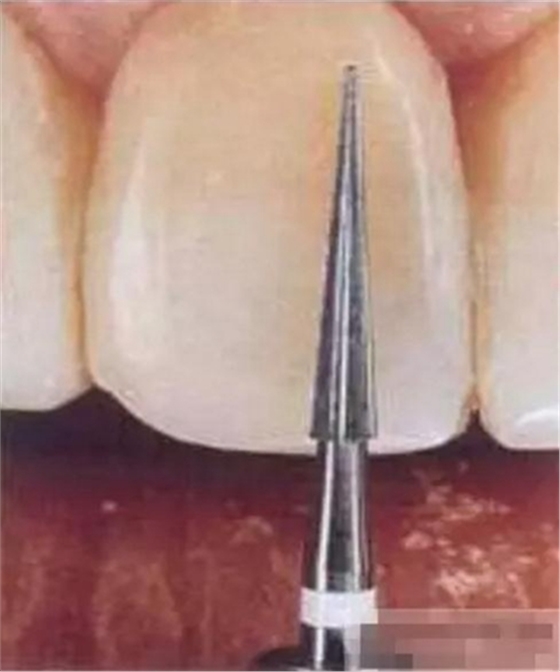

選擇合適的完成鉆制備根管,

通常深入到根管的1/2至2/3處

在使用根管纖維樁時(shí)根管預(yù)備的深度應(yīng)該是多少呢?

在回答這個(gè)問題前,首先應(yīng)該了解根管內(nèi)的粘接狀況。最佳的粘接效果發(fā)生于根管的冠1/3和中1/3。由于根1/3的牙本質(zhì)小管往往不能充分敞開,此區(qū)域幾乎沒有粘接作用發(fā)生,所以,根管纖維樁放置的深度無需超過根中1/3。同樣重要的是,根管預(yù)備時(shí)鉆的速度不要過快,防止飛濺的牙膠粘在根管內(nèi)壁上。所以,根管壁的清理也很重要,以確保牙本質(zhì)小管充分開放。Dr.Vanini使用噴砂和酸蝕來充分清理根管壁和窩洞。研究顯示,粘接劑的作用也很重要,粘接根管纖維樁要求使用滲透力強(qiáng)粘結(jié)作用好的粘接劑。